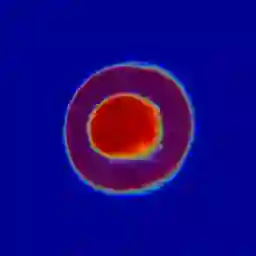

Manual medical image segmentation is subjective and suffers from annotator-related bias, which can be mimicked or amplified by deep learning methods. Recently, researchers have suggested that such bias is the combination of the annotator preference and stochastic error, which are modeled by convolution blocks located after decoder and pixel-wise independent Gaussian distribution, respectively. It is unlikely that convolution blocks can effectively model the varying degrees of preference at the full resolution level. Additionally, the independent pixel-wise Gaussian distribution disregards pixel correlations, leading to a discontinuous boundary. This paper proposes a Transformer-based Annotation Bias-aware (TAB) medical image segmentation model, which tackles the annotator-related bias via modeling annotator preference and stochastic errors. TAB employs the Transformer with learnable queries to extract the different preference-focused features. This enables TAB to produce segmentation with various preferences simultaneously using a single segmentation head. Moreover, TAB takes the multivariant normal distribution assumption that models pixel correlations, and learns the annotation distribution to disentangle the stochastic error. We evaluated our TAB on an OD/OC segmentation benchmark annotated by six annotators. Our results suggest that TAB outperforms existing medical image segmentation models which take into account the annotator-related bias.